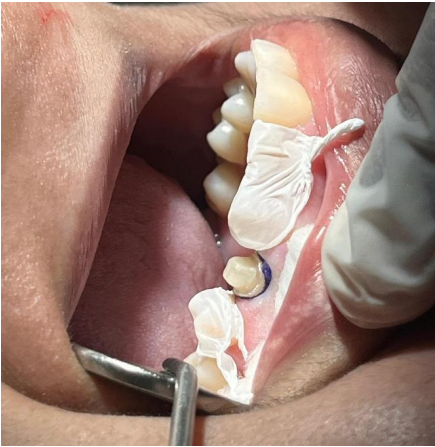

2ª Sessão: Foi realizada a prova clínica da coroa confeccionada pelo laboratório, sendo posicionado e avaliado quanto à adaptação marginal, pontos de contato proximais, e oclusão. Foram feitas pequenas adequações, para ajuste oclusal, e reencaminhada ao laboratório protético para o processo final da coroa.

Figura – Teste clínico